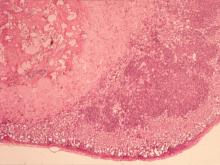

肺臟:雙葉皆有多發局部性黃白色圓形突起結節,直徑約2-4 mm大小並深入實質;肺右葉與胸壁、橫膈膜粘連。 4.

肺:肺水腫,局部肉芽腫病灶,壞死區內有大量炎症細胞浸潤,以單核球和巨大細胞為主。在許多Giant cell中可見褐色不易染色的黴菌菌體。局部壞死區近血管處可見膽固醇裂隙浸潤。 2.

脾與淋巴結:多發局部肉芽腫,淋巴球減少流失,大量吞噬球及巨大細胞浸潤於壞死灶,內含多數黴菌樣菌體。 4.